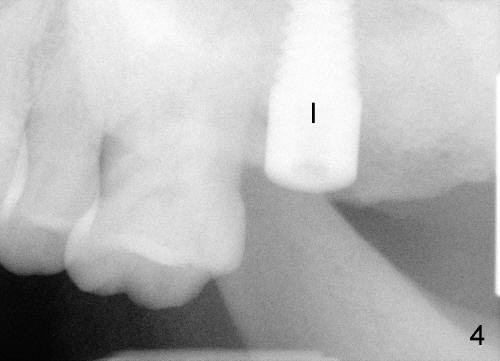

A 50-year-old lady presented to clinic with chief complaint of a loose tooth upper left.  The tooth #15 has complex endo-perio disease (Fig.1,2).  It was extracted on November 29, 2012.  She returned to clinic for implant placement on January 28, 2013.  Under local anesthesia, osteotomy was prepared with combination of bone expansion and drilling (Fig.3: 4x14 tapered drill).  She was not comfortable with tapping.  Finally, Tatum tapered implant (6x14) was placed (Fig.4) with 35 Ncm.  She felt dizzy when she stood up from dental chair. She felt better by the evening of January 29, 2013.  But the following morning, she did not feel good.  She wonders when the symptom will disappears.